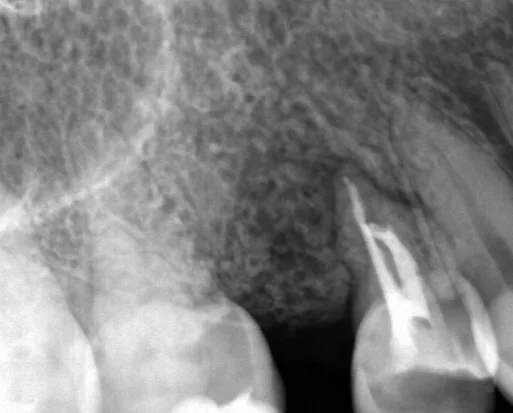

そして神経の治療を1回行って、2回目で最終的なお薬を詰めました。

根が2本ありましたが、1本がやたらと曲がっていたため、非常に難しい根管治療でした。

ちなみに、術前術後でのレントゲンと口腔内写真がそれぞれこちらです。